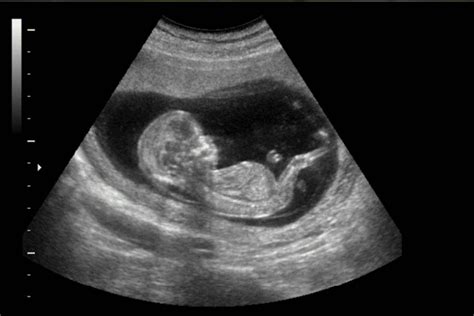

I primi movimenti fetali sono un momento atteso con trepidazione dalle future madri. Generalmente, questi movimenti sottili possono essere percepiti tra la 18ª e la 22ª settimana di gravidanza, sebbene in alcune donne possano manifestarsi anche prima. La capacità di riconoscere questi primi segnali può variare notevolmente, specialmente tra la prima gravidanza e quelle successive. Nei primi periodi gestazionali, le sensazioni possono essere meno evidenti o percepite più tardi, poiché la madre potrebbe non identificare immediatamente le delicate vibrazioni come movimenti del bambino. È fondamentale ricordare che ogni gravidanza è un'esperienza unica, e di conseguenza, anche le tempistiche e la percezione dei movimenti fetali possono differire significativamente da donna a donna.

Man mano che la gravidanza progredisce, i movimenti del feto subiscono variazioni significative, riflettendo la sua crescita e il suo sviluppo all'interno dell'utero.

- Tra la 20ª e la 26ª settimana: La donna inizia a percepire i primi "sfarfallii", spesso avvertiti in momenti di relax, quando è in una posizione comoda e presta attenzione.

- Tra la 26ª e la 30ª settimana: I movimenti diventano più distinti. Questo è dovuto in parte a una riduzione del liquido amniotico, che rende i movimenti meno ammortizzati. In questa fase, potrebbero essere visibili cambiamenti nella forma della pancia della madre.

- Tra la 30ª e la 35ª settimana: I movimenti si fanno più evidenti ma, al contempo, tendono a rallentare. Ciò è conseguenza dell'aumento delle dimensioni del bambino e della conseguente limitazione dello spazio all'interno dell'utero. La maggior parte dei bambini si posiziona in presentazione cefalica, con la testa rivolta verso il basso, la posizione ideale per il parto naturale.

- Dalla 35ª alla 40ª settimana: Nonostante lo spazio limitato, i movimenti continuano a essere percepibili. In questa fase avanzata della gravidanza, si instaura un legame quasi simbiotico tra madre e bambino, intensificato dall'emotività legata all'attesa del parto. Talvolta, questi movimenti possono indurre piccole contrazioni uterine, generalmente non dolorose.